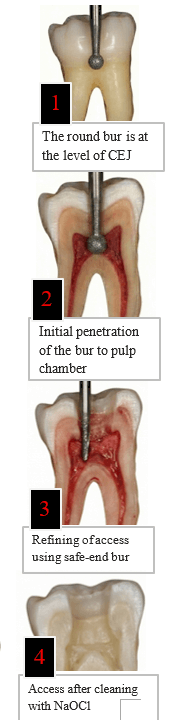

Method: Begin with a conservative, small opening and enlarge gradually.

Why: Avoids excessive removal of tooth structure which compromises strength.

Tool: Use a round diamond or carbide bur for the initial hole.

Ensure placement aligns with the natural pulp chamber.

Definition: “Catches” are irregularities in walls where instruments get stuck.

Risk: Causes ledging or perforation.

Action: Use a round bur to smoothen internal walls (un-roofing the chamber). Verify smoothness with a fine endodontic explorer.